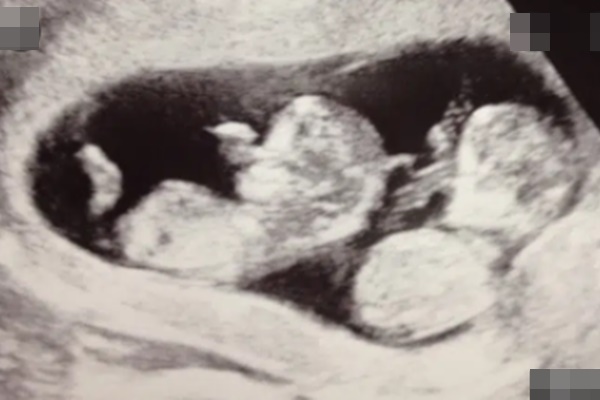

Song, chỉ hai tháng sau khi sinh Blake, chị Melanie phát hiện mình có thai lần thứ 3. Lúc siêu âm ở tuần thứ 8, bà mẹ được thông báo là có 2 nhịp tim. Nhưng đến tuần thứ 12, vợ chồng chị Melanie sửng sốt khi nghe bác sĩ báo họ sắp sửa chào đón 3 em bé, trong đó có 1 cặp song sinh.

Từ đó, chị Melanie phải đi siêu âm hai tuần một lần để bác sĩ theo dõi chặt chẽ, vì họ lo ngại rằng em bé có khả năng sẽ bị mắc hội chứng truyền máu song thai – một tình trạng khiến lưu lượng máu từ nhau thai phân bổ đến hai em bé không đồng đều

Phụ nữ có tử cung đôi vốn đã hiếm gặp với tỉ lệ là 1/3.000 người, nhưng sinh 3 em bé trong đó có một cặp song sinh ở một bên tử cung thì lại càng hiếm thấy. Theo các chuyên gia, tỉ lệ này phải lên đến khoảng 1/1.000.000 lần. Trên thế giới hiện nay mới chỉ có 4 trường hợp này và bác sĩ tin rằng chị Melanie là trường hợp đầu tiên ở nước Anh.